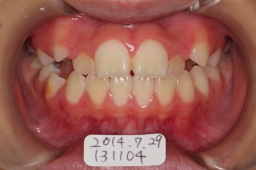

2014年07月29日 初診

上顎前歯の叢生と交叉咬合